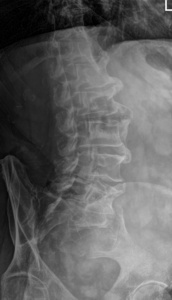

Plain film x-rays of the lumbosacral spine with obliques demonstrated flowing left-sided ligament ossification with ankylosis extending from L1-L4 with preservation of disc height, mild-to-moderate left facet arthrosis at L5-S1 and anterior ligament ossification ankylosis of the L5-S1 disc space, mild levoscoliosis, apex at L3-L4 and low left hemipelvis. See Figures 1 to 4.